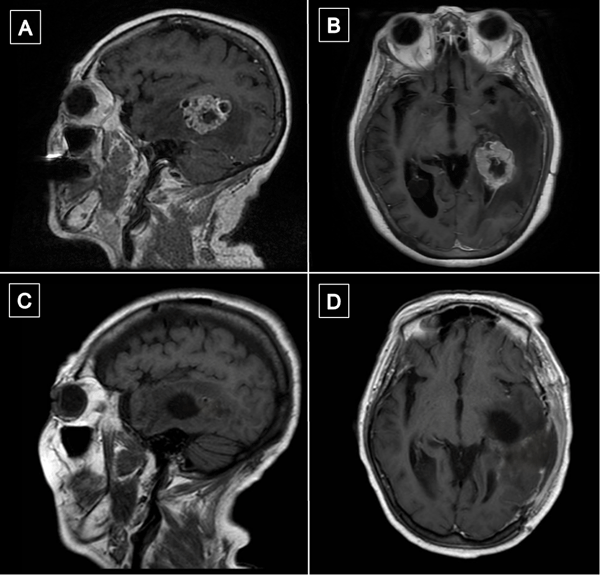

La resonancia magnética (RM) de encéfalo con gadolinio evidenció una lesión expansiva heterogénea, con áreas centrales de aspecto quístico y degeneración necrótica, localizada en la topografía temporomesial izquierda de aproximadamente 28 × 27 mm en plano axial y 29 × 26 mm en plano coronal, con realce heterogéneo tras la administración de contraste endovenoso. En secuencia de susceptibilidad magnética presentaba signos de restos de hemosiderina y/o microcalcificaciones. En el asta occipital y el atrio ipsilateral del ventrículo lateral, se evidenciaron formaciones quísticas con refuerzo periférico. La lesión descripta presentaba edema perilesional que comprometía el lóbulo temporal izquierdo y la región parietoccipital ipsilateral. Además, se observó dilatación del tercer ventrículo y ventrículo lateral homolateral. Las cisternas perimesencefálicas se encontraban libres, y las estructuras de la línea media, centradas. Las imágenes obtenidas eran sugestivas de una lesión de origen glial de alto grado (Figura 1). Se complementó con tractografía en la que se observó una disminución de la fracción de anisotropía a nivel del septum sagital con disrupción de las fibras de los tractos arcuato, frontooccipital inferior y longitudinal inferior izquierdo (Figura 2).

Figura 1. RM preoperatoria con contraste endovenoso. A y B) RM de encéfalo, cortes axial y sagital, respectivamente, en secuencia T1 contrastada, que evidencia lesión expansiva con realce heterogéneo localizada en topografía temporomesial izquierda. C) Corte axial en secuencia T2, se muestra heterogeneidad de la lesión con áreas centrales de aspecto quístico y degeneración necrótica. D) Corte axial en secuencia FLAIR que evidencia edema perilesional que compromete lóbulo temporal izquierdo y región parietooccipital ipsilateral.

Figura 6. Comparación de resonancias magnéticas pre y postquirúrgicas. A y B) RM prequirúrgica de encéfalo, cortes axial y sagital, respectivamente, en secuencia T1 contrastada, se evidencia lesión expansiva con realce heterogéneo localizada en topografía temporomesial izquierda. C y D) RM de encéfalo con gadolinio realizada aproximadamente un mes luego de la intervención quirúrgica. Cortes axial y sagital, respectivamente, en secuencia T1 contrastada en la que se evidencia en región temporomesial izquierda un área de señal líquida con signos de gliosis periférica, sin evidencia de lesión tumoral residual.